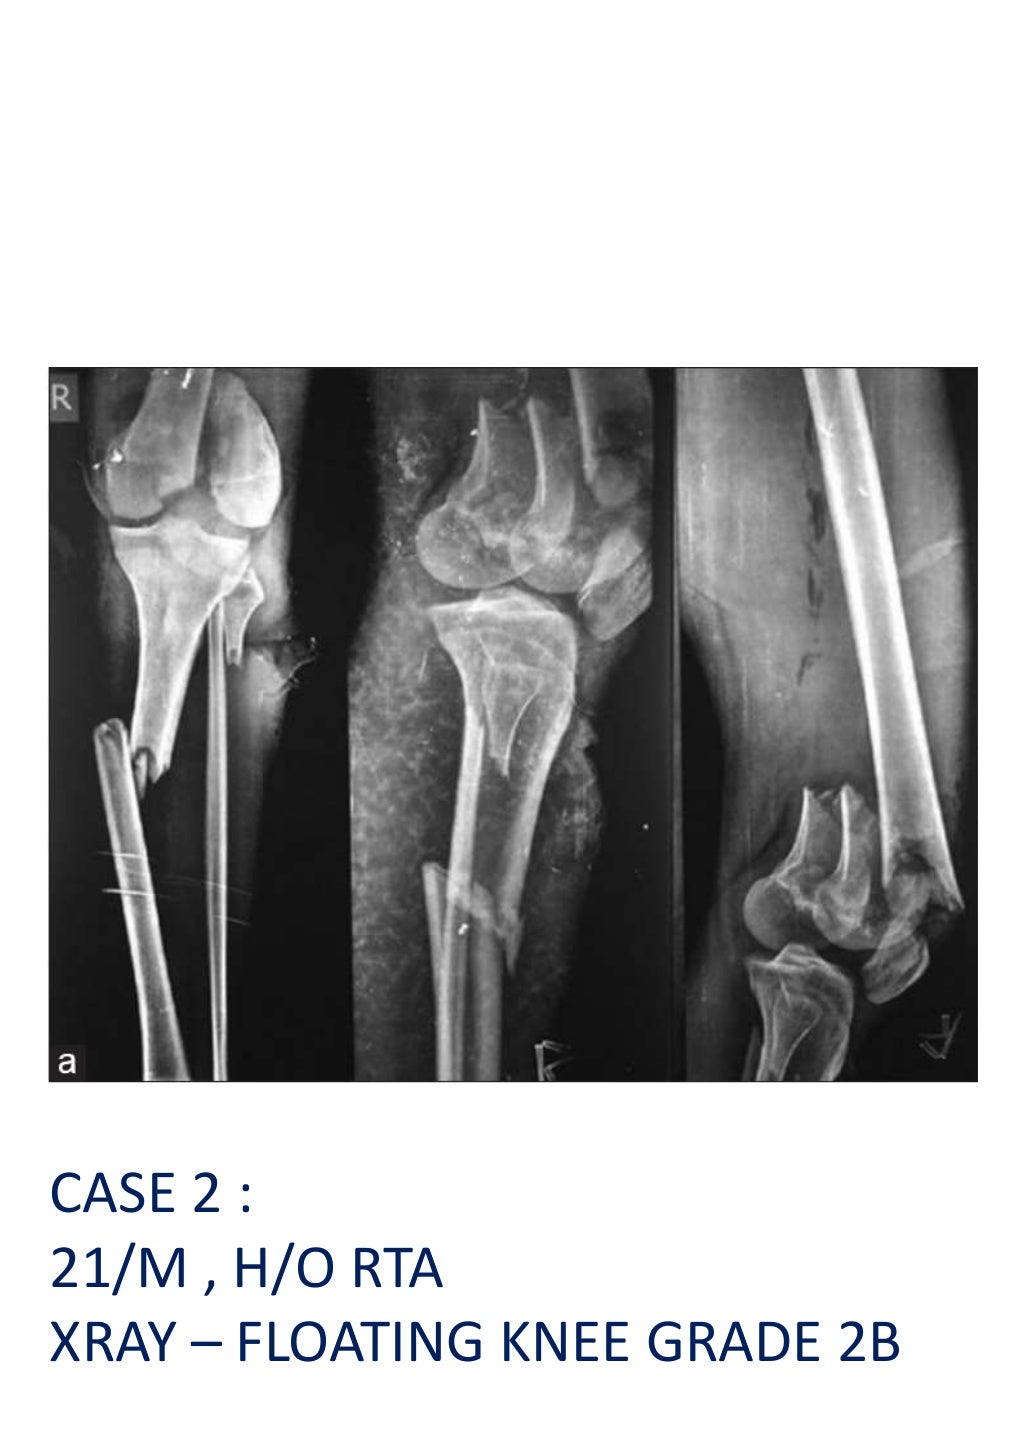

Floating Knee Classification Ppt . Floating knee is a flail knee joint resulting from fractures of the shafts or adjacent metaphyses of the femur and ipsilateral tibia (see image below). Floating knee injuries may include a. The document summarizes key information about floating knee injuries, which involve concurrent fractures of the femur and tibia near the knee. And type iii, patella involved. Type ii injuries were subdivided into. These injuries have high rates of open. The floating knees were classified as three types: Management of the floating knee in. This is a pediatric classification system that first classifies the region of the fracture and whether it is an open or closed fracture. In 1975, blake and mcbryde established the concept of ‘floating knee’ to describe ipsilateral fractures of the femur and tibia.¹ this combination is much more than a bone lesion;. Type ii, articular surface involved; This document discusses floating knee injuries, which involve ipsilateral fractures of the femur and tibia. Download scientific diagram | fraser's classification of floating knee.